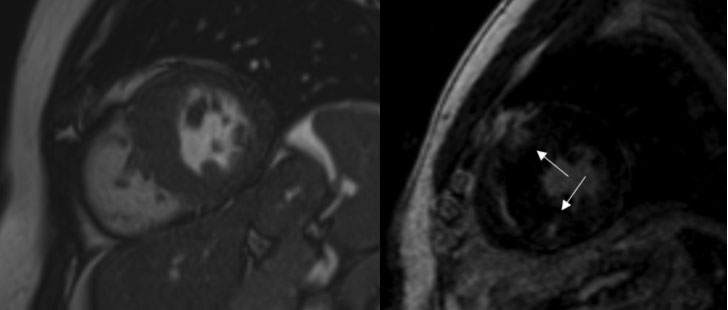

- Cardiomiopatia Ipertrofica: la cardiomiopatia ipertrofica è una condizione patologica su base genetica caratterizzata da un’estrema ipertrofia miocardica. Lo studio con RMNC permette di valutare l’estensione dei segmenti ipertrofici (ipertrofia globale, settale, apicale o medio ventricolare), di valutare la presenza di elementi associati a rischio aritmogeno come l’ispessimento ventricolare sinistro >30 mm, la dilatazione aneurismatica apicale, l’ostruzione all’eiezione ventricolare sinistra, la presenza e l’estensione di ischemia/fibrosi. Tutti questi elementi si sono rivelati forti predittori di morte improvvisa in pazienti affetti da questa condizione (5, Figura 1).

- Displasia Aritmogena del ventricolo destro: la displasia aritmogena del ventricolo destro è una patologia genetica del muscolo cardiaco caratterizzata da una sostituzione fibro-adiposa del miocardio ventricolare destro ma che in percentuale variabile può interessare anche il ventricolo sinistro. In accordo la Società Europea di Cardiologia la diagnosi si basa sulla presenza di criteri diagnostici maggiori e minori che comprendono elementi strutturali, istologici, elettrocardiografici e clinici come la storia familiare di morte improvvisa. In questo contesto la risonanza magnetica cardiaca gioca un ruolo fondamentale nella definizione delle dimensioni, della funzione globale, della cinetica segmentaria del ventricolo destro e della caratterizzazione istologica. In particolare la dimostrazione di sostituzione fibro-adiposa mediante apposite sequenze, ha presentato in vari studi un’ottima correlazione con l’inducibilità di tachicardia ventricolare allo studio elettrofisiologico di vulnerabilità ventricolare guidando la successiva scelta di impiantare un ICD (6, Figura 2).

Cardiomiopatia ipertrofica con evidenza di aree di late gadolinium enhancement in corrispondenza delle giunzioni con la parete libera ventricolare destra indicative di sostituzione fibrotica.

Displasia aritmogena biventricolare associata ad area di infiltrazione adiposa della parete laterale distale e dell’apice del ventricolo sinistro.